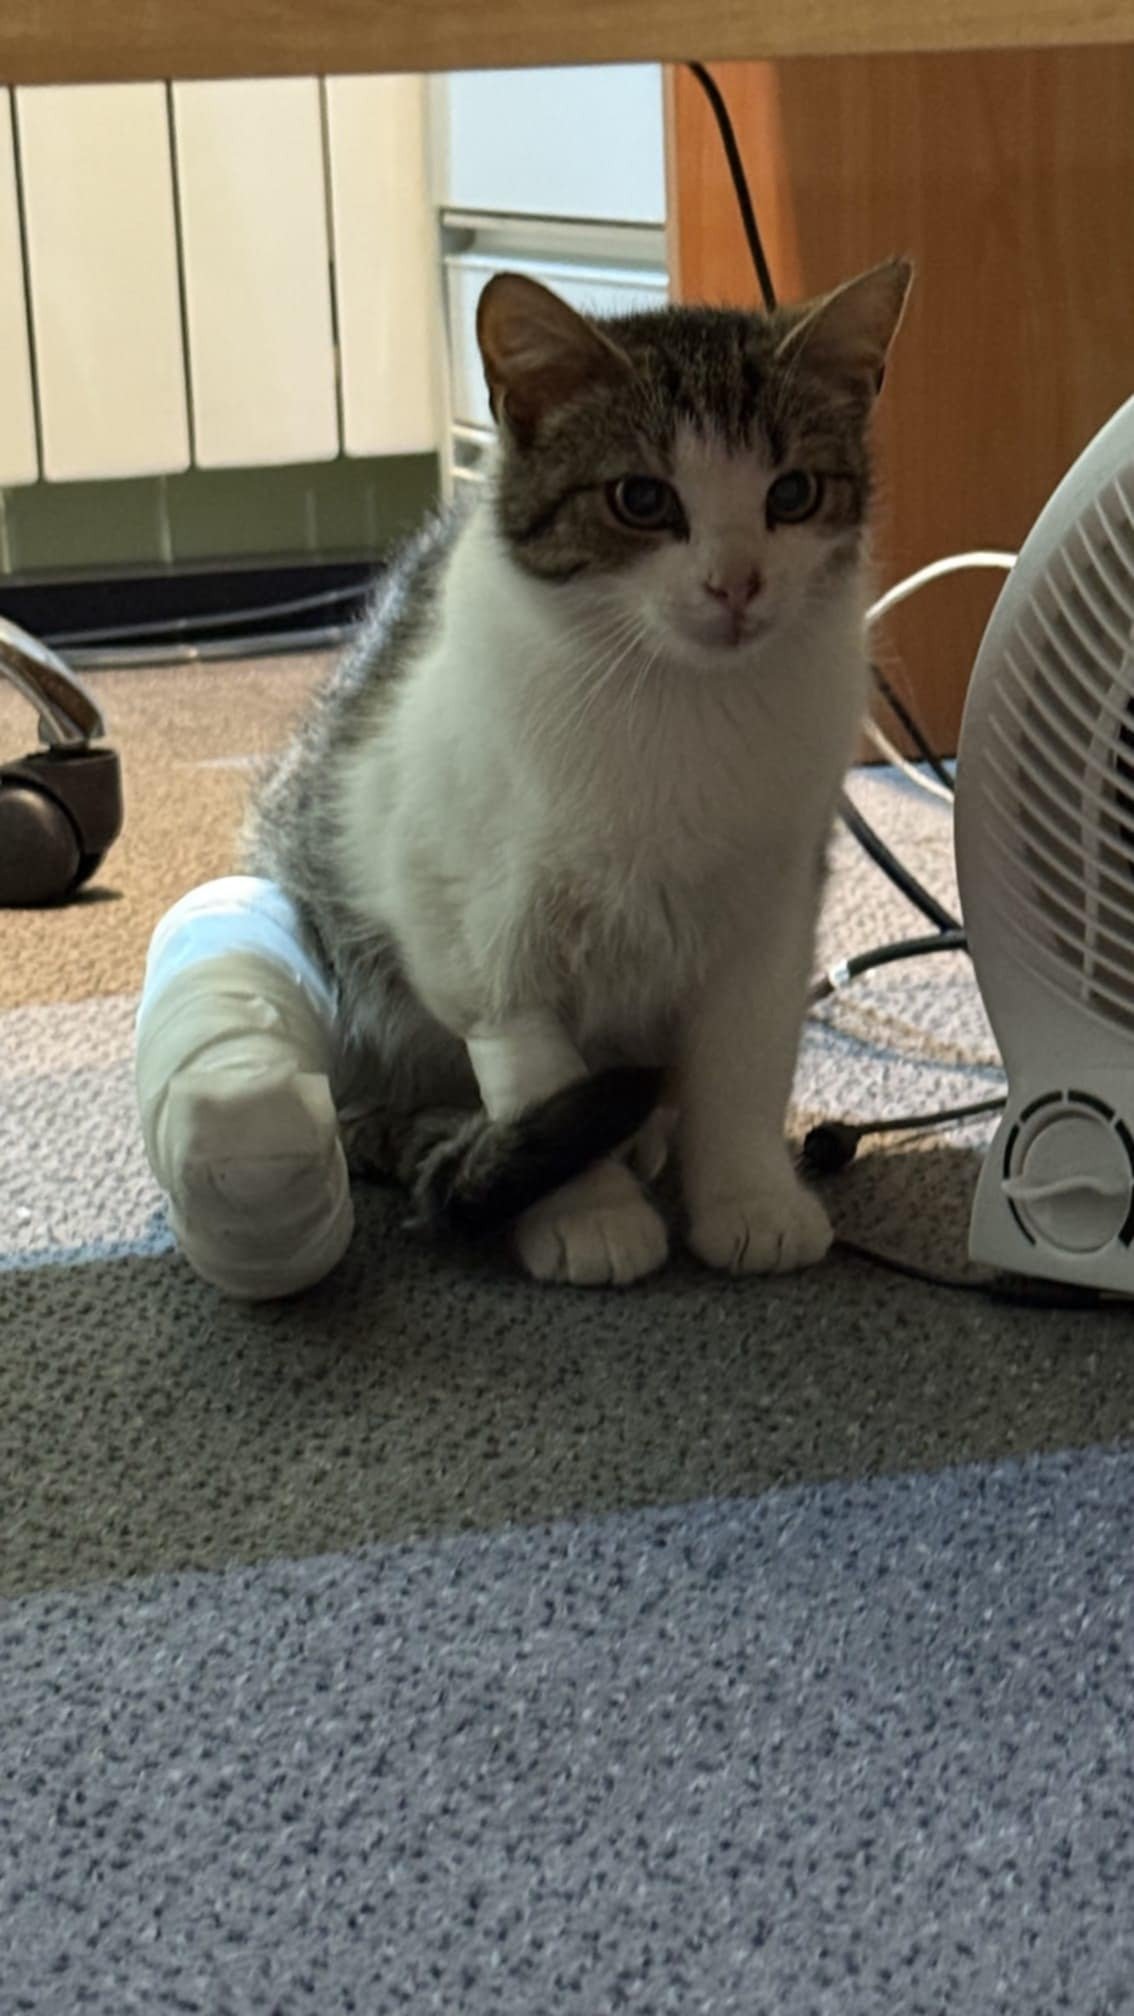

Po paru dniach Pracownicy hotelu zauważyli, że koteczka ma problem z tylną, prawą łapką. Wyraźnie kulała i powłóczyła nią.

Malutka ma więc założony gips i opatrunek. Oczywiście nie wróciła na ulicę, została z nami :-)

Na najbliższy piątek, tj. 16 maja koteczka ma umówiony zabieg artrodezy,